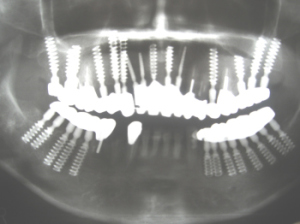

| 6年後の2007年に来院時の写真。 右下の自分の歯がとれたと来院。 インプラント部分で何でも噛めると言っていました。インプラントは極めて良好。 |